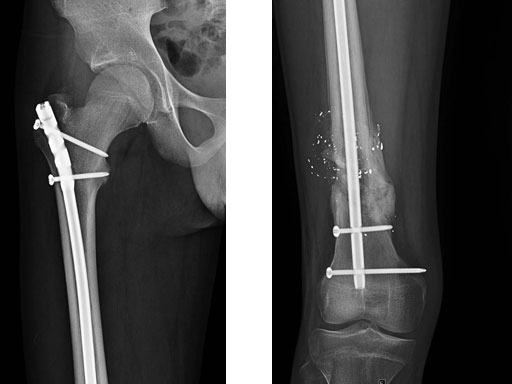

A 15-year-old male sustained an extensive soft-tissue injury with loss of bone after a gunshot (low-velocity, large caliber bullet). Neurovascular status intact, large exit wound.

The open injury (Fig 1) was debrided and cleansed. There was missing bone from the femur. Open but rapidly closing growth plates.

Fig 1 Preoperative lateral x-ray.